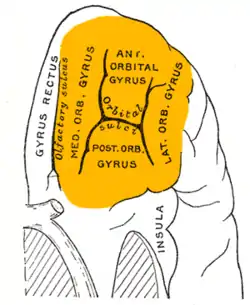

Orbital surface of left frontal lobe. | |

The OFC is divided into multiple broad regions distinguished by cytoarchitecture, including brodmann area 47/12, brodmann area 11, brodmann area 14, brodmann area 13, and brodmann area 10.[14] Four gyri are split by a complex of sulci that most frequently resembles a "H" or a "K" pattern. Extending along the rostro-caudal axis, two sulci, the lateral and orbital sulci, are usually connected by the transverse orbital sulcus, which extends along a medial-lateral axis. Most medially, the medial orbital gyrus is separated from the gyrus rectus by the olfactory sulcus.[15] Anteriorly, both the gyrus rectus and the medial part of the medial orbital gyrus consist of area 11(m), and posteriorly, area 14. The posterior orbital gyrus consists mostly of area 13, and is bordered medially and laterally by the anterior limbs of the medial and lateral orbital sulci. Area 11 makes up a large part of the OFC involving both the lateral parts of the medial orbital gyrus as well as the anterior orbital gyrus. The lateral orbital gyrus consists mostly of area 47/12.[14] Most of the OFC is granular, although the caudal parts of area 13 and area 14 are agranular.[16] These caudal regions, which sometimes includes parts of the insular cortex, responds primarily to unprocessed sensory cues.[17]